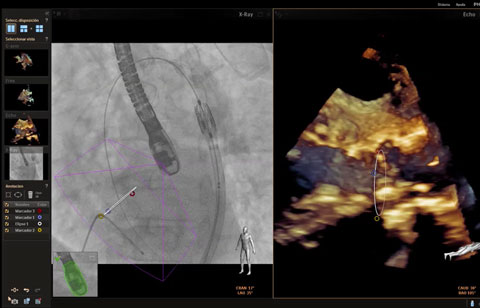

تم تشخيص أحد المرضى لديك بتضيّق في الصمام الأورطي المصحوب بأعراض. يبلغ عمر المريضة 85 عامًا وهي تعاني من السكري وارتفاع ضغط الدم. أنت تدرك خطورة وضعها الصحي ما يجعلها غير مناسبة لجراحة القلب ولكن يسمح لها بأن تكون مرشحة لاستبدال الصمام الأورطي باستخدام القسطرة (TAVR). في يومنا هذا، تمنح حلول التصوير المبتكرة والأجهزة التي تعمل عن طريق الجلد الأمل لبعض المرضى الذين لا تتوفر لهم حتى الآن أي خيارات علاجية أخرى.